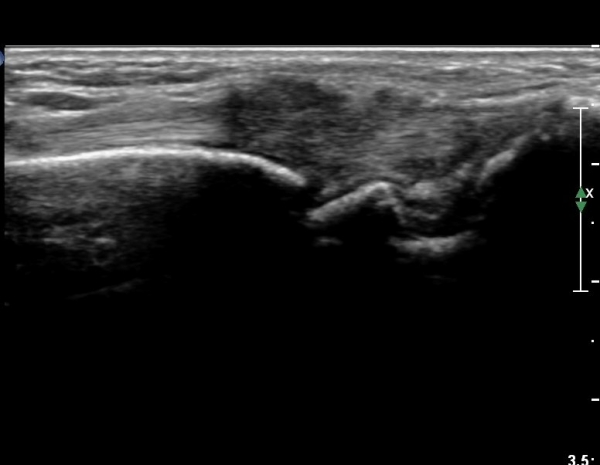

ŽÃËÀÚ¸¦¾à°£ ¿äÃøÀ¸·Î À̵¿ÇÏ¿© Àå¿äÃø¼ö±Ù½Å°Ç Á¾´Ü¸é°Ë»ç¿¡¼­ Àå¿äÃø¼ö±Ù½Å°ÇÀÇ

ºÎÁ¾ÀÌ °üÂûµÇ°í ½ÅÀü°Ç Ç¥Ãþ¿¡¼­ À幫Áö½ÅÀü°ÇÀÌ °üÂûµÈ´Ù(»çÁø 2).